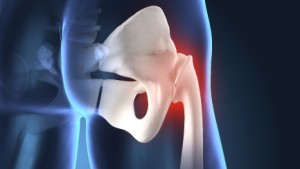

Our hips are ball and socket joints, with the end of our leg bone (femoral head) fitting neatly into the hip socket (acetabulum). Both of these are covered with cartilage, with synovial fluid lubricating them. Over time, our wellbeing may feel the effects of this cartilage being worn away and inflamed, which is a form of arthritis. We can feel pain as the cartilage on the end of the bones rubs against each other. When there is inflammation of the synovial lining then this could be down to rheumatoid arthritis. Both of these conditions can be very painful, especially if cartilage wears completely away, or the lubricating lining that’s meant to reduce friction becomes increasingly inflamed.

Pain is the common factor, as are joint stiffness and groin pain that limits the range of motion of our hips. Pain may occur at different times though, with osteoarthritis getting worse when we move the joint or if we have a very busy day. With rheumatoid arthritis we may feel sore in the mornings but gentle activity can ease symptoms as the day progresses. To establish whether we have arthritis or not, doctors will perform some mobility tests on our hips. This normally involves seeing how much we can move the joint and how well we stand and walk. Surgery isn’t usually the first option for arthritis, and GPs usually opt for pain management and physiotherapy, but depending on the severity of the syndrome we could be put forward for a hip replacement.